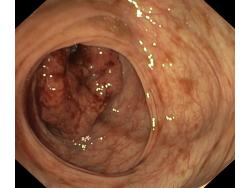

Nowotwory przewodu pokarmowego